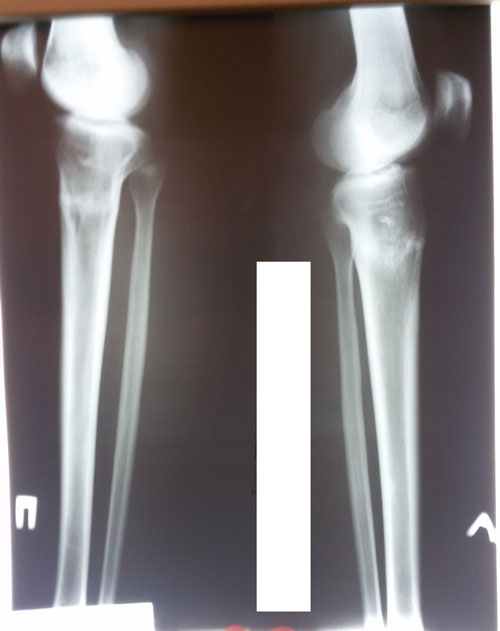

Рентген контроль в 2 месяца с момента снятия аппаратов.

Здравствуйте, А.! По рентгену всё отлично! Ограничений в нагрузках нет, каблуки разрешены. Для разработки суставов - массаж, гимнастика, очень хорошо помогает боди балет. Хорошие результаты после его занятий, наши пациентки оценили.